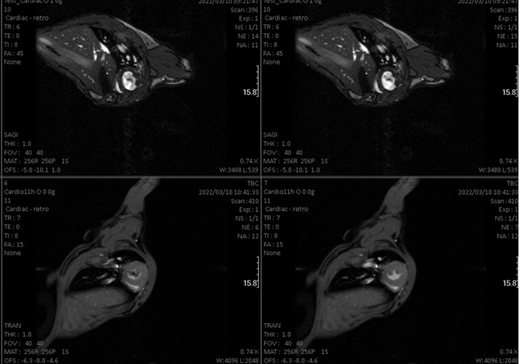

- Qualitative and quantitative studies (relaxation times T1 and T2 and even making maps) at the brain level and other organs.Cardiological sequences: diffusion, determination of blood volume…

- Thanks to the possibility of rotating the equipment in a vertical position, images of plants can be obtained (because by their nature, they have to be in a vertical orientation, such as a stem). Ex-vivo studies can also be carried out vertically and in this way we maintain the integrity of the organ (eg heart).